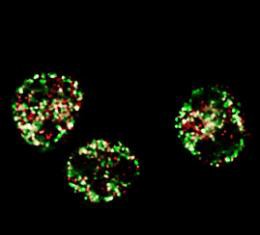

Los científicos resuelven el rompecabezas de cáncer de próstata

Los científicos han puesto de manifiesto una ruta completamente nueva en la que las hormonas masculinas, andrógenos, que impulsan el crecimiento del cáncer de...